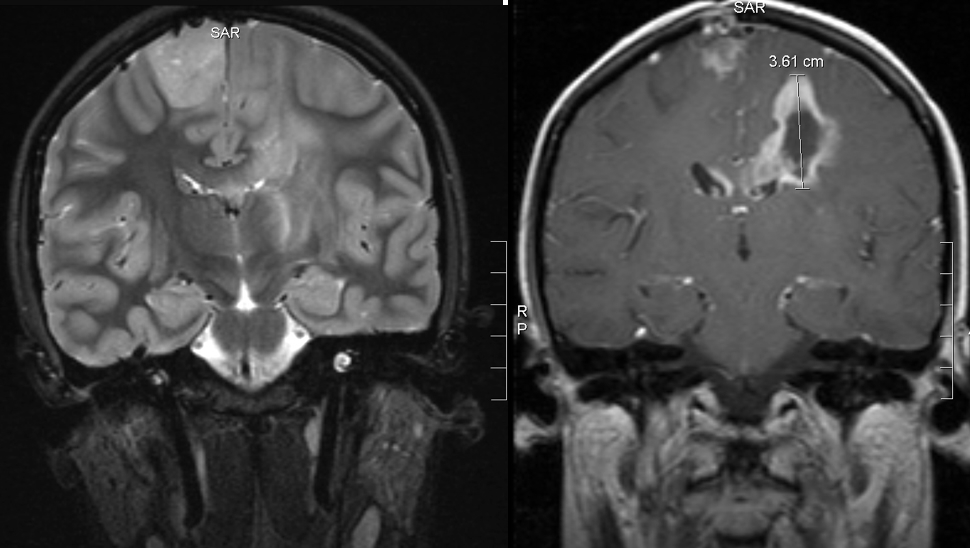

These images show that the rest of the tumor hadn’t seemed to notice there’d been treatment going on:

Back view MRI before and after treatment

(l) 27 Oct 2006: a month after her first MRI, before the biopsy, 3 weeks before treatment began

(r) 27 Feb 2007: 1.5 months after the end of radiation and vincristine-cisplatin. The dark center in the tumor is necrosis (dead tissue), which could be from radiation; it’s also a hallmark of glioblastoma multiforme (GBM): a GBM grows so quickly its blood supply can’t keep up with it, and the center dies off.